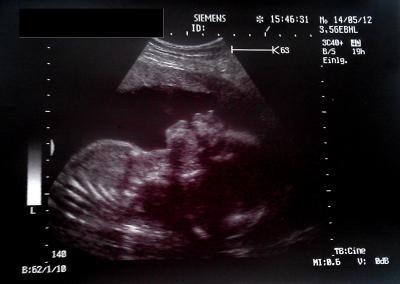

Hallooo Mädels, ich hatte heute meinen regulären Frauenarzttermin. Es ist alles in Ordnung, mir gehts nach Nierenstau und schmerzen besser. Magnesium hat angeschlagen, habe wieder eine normale Verdauung und schmerzen auch nur selten. Jetzt kann ich die Schwangerschaft wieder richtig geniesen. Heute war Urin und Gewicht, sowie Blutdruck in bester Ordnung. Mir wurde allerdings Blut abgenommen, da mein Arzt einen Eisenmangel vermutet, das ich etwas blass bin, wobei ich das IMMER bin. Naja sicher ist sicher. Dem kleinen gehts blendend, hat mich während der Untersuchung mächtig oft getreten, er mag das wohl nicht. Er ließ sich nochmal zwischen die Beine sehen, so das ich seinen Penis nun auch zu Gesicht bekommen habe. Er hat einen Kopfumfang von 21 cm und der Oberschenkel ist 4 cm lang. Er hat mir leider nicht gesagat, wie groß der kleine jetzt momentan insgesamt ist, aber ich hab ein tolles Bildchen bekommen. Sieht so ein bisschen aus, als würde er lachen :-) Liebe Grüßeeeee

Bild zu Heute Frauenarzttermin und Bildchen bekommen :-) - Forum für September - Mamis

Wenn der Oberschenkelknochen 4cm ist, dann ist dein Krümel 28cm groß, also etwa... Musst immer FL x7 rechnen... =) Schönes Bildchen hast du bekommen =)

Danke, hab es gerade gesehen im Mutterpass, da steht 42, wahrscheinlich mm, also 4,2 cm. Ich hab gerade mal gerechnet, Baby dürfte 29,4 cm groß sein. Danke dir nochmal :-)

Huhu Sarah, meine FA hat mir bei meiner letzten Untersuchung (19+4) auch nicht mehr sagen können oder wollen wir groß und schwer der kleine ist. Ich hab dann rausgefunden das FL die Länge des Oberschenkelknochens ist...das man dann mal 7 rechnen muss um die Größe des kleinen zu errechnen wusste ich auch nicht...danke für den Tipp Leider kenn ich nur den Längs bzw. Querurchmesser des Köpfchen meines Kindes, hab mir dann anhand der Berechnung eines Kreises ungefähr errechnen können das der Kopfumfang ca 19 cm lag. Das Bild ist süss....meine FA macht bei jeder Untersuchung auch Ultraschall und so bekomm ich jeden Monat ein Bildchen